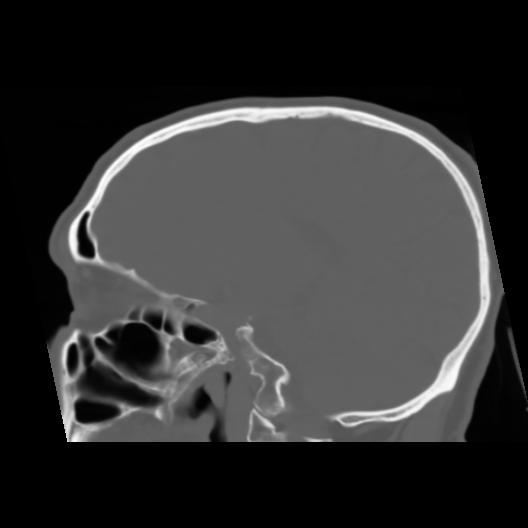

6 CEREBRO,,Sagittal,3.000,CEREBRO,Sagittal,